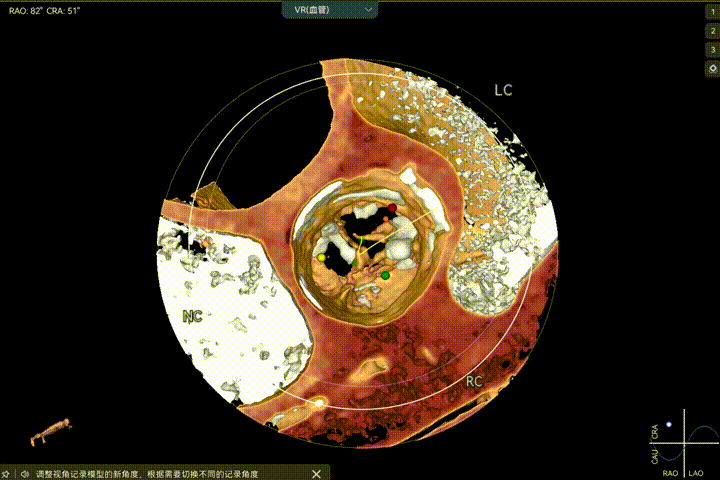

主动脉瓣环周长径21.9mm,小瓣环,LVOT直筒型结构;三叶瓣,左右融合(功能型二叶瓣),瓣叶轻微增厚并重度钙化,钙化主要分布在无冠窦瓣叶边缘及左右交界融合处,瓣上限制较重。

Step 9.CuspOverlap体位验证缘对缘对齐,挂钩位于最右方,基本避开冠脉开口